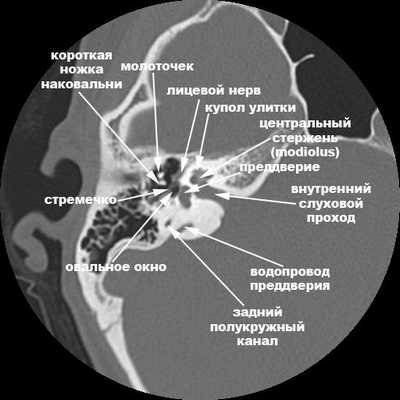

КТ-анатомия височных костей

Компьютерная томография височных костей в норме показывает следующие анатомические структуры:

Нижнюю часть барабанной полости (гипотимпанум) можно изучить только с помощью компьютерного сканирования. Отдел содержит важные анатомические структуры - три полукружных канала (латеральный, задний, верхний), улитку, преддверье.

улитка, преддверие, передний и задний полукружный каналы;

слуховые косточки среднего уха;